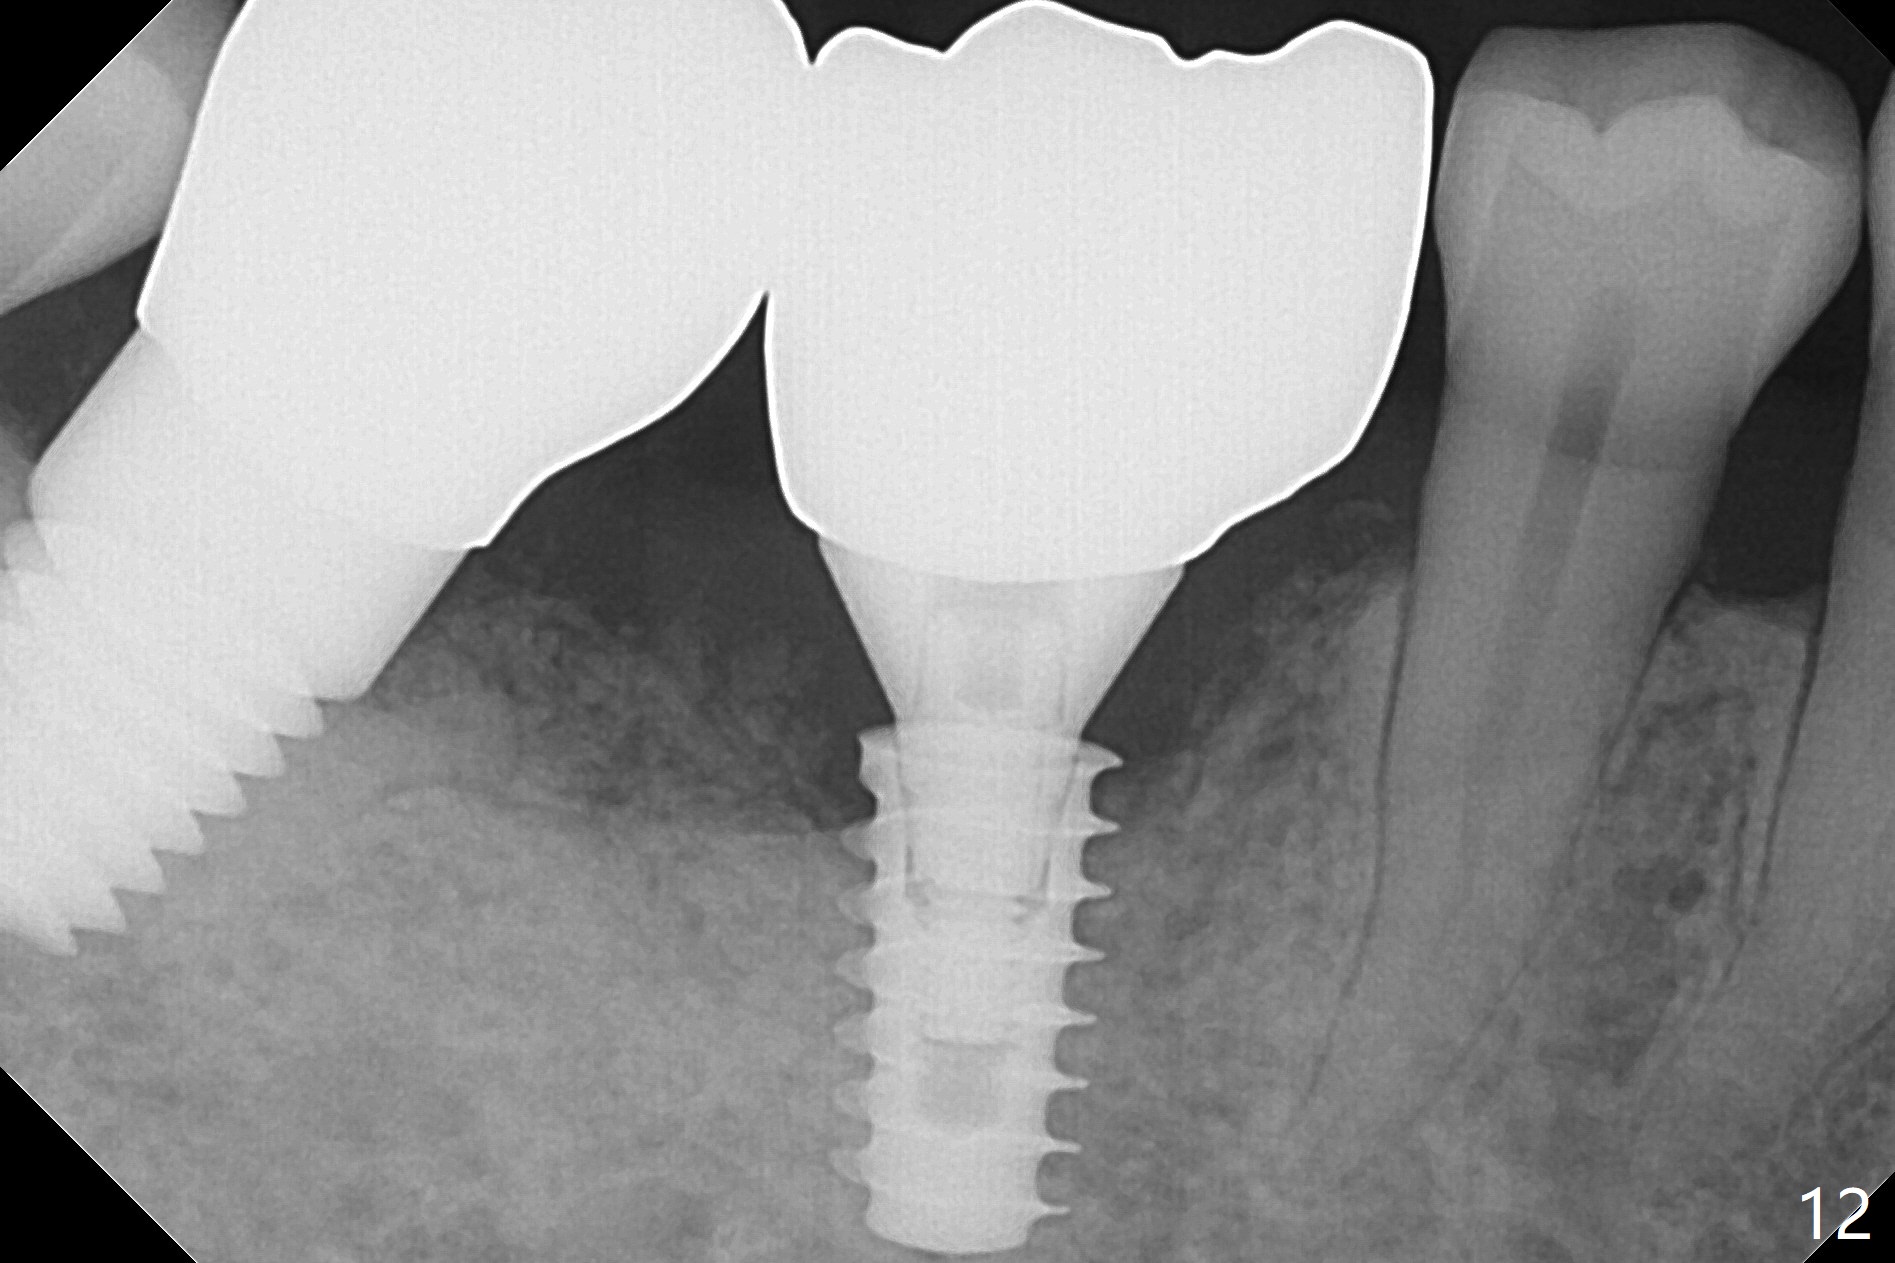

Extraction shows the large distal socket (Fig.1 D) and the thin and low septum (*) of the tooth #30. After Magic Split test confirms hard bone, osteotomy is initiated with 1.6 mm pilot drill with 11 mm stopper (Fig.2); there is 2.7 mm distance to the Inferior Alveolar Canal. Following Marking Bur, a 4.8 mm Magic Drill is used to finish the osteotomy with difficulty because of hard bone and ineffective local anesthesia due to infection. A 5x9 mm "dummy" implant is placed to determine the placement level relative to the distal crest (Fig.3 *). After removal of the dummy implant, an authentic one with the same dimension is placed with packing abundant allograft (.5-1.5 mm) and Osteogen (Fig.4 *); it appears that 4 to 5 threads (fins) of the implant (arrowheads) are engaged to the native bone for primary stability (>40 Ncm). Later more bone graft is placed distally (Fig.5 arrow). With the short implant placed not so deep, there is 6-7 mm clearance from the underlying canal (Fig.6). The patient is doing well 7 days postop (Fig.7). He feels that the provisional is too bulky buccally for the first 2 days postop. The buccal margin will be trimmed in another 2 weeks (dashed line). The patient in fact masticates on the right side postop. By the time he returns for provisional revision 1 months 10 days postop, he has mild pain. There is food entrapment. The provisional and the abutment are slightly loose, whereas the implant is stable with healing socket (Fig.8). A healing abutment is placed. The implant appears unstable nearly 5.5 months postop. The gap between the bone and implant seems to be large (Fig.9). The implant should have been larger and longer for fast healing. A healing screw is used instead. The site heals 10 months postop with an increase in bone density around the implant (Fig.10.) Prior to cementation of the final crown, the abutment is minimally exposed (Fig.11 (6.5x5.7(3) mm)). In fact the abutment screw becomes loose 2 months post cementation (1 year postop); it appears that crown/implant ratio is unfavorable (Fig.12). The implant is slightly placed mesially (cantilever). The patient cannot chew on the left. The tooth #19 is periodontally affected and the tooth #18 is missing. When bone loss is severe, the implant should be as large as possible and preferably tissue-level. The abutment screw is re-loosening 1.5 years post cementation (4 months post #19 socket preservation, Fig.13). The crown/implant ratio at #31 is more favorable than that at #30 (compare black lines). The crown at #31 has large contact area with the tissue-level implant (external), whereas the contact between the abutment and the bone-level implant is much less (internal). To prevent the abutment screw re-loosening (turning) in function, a screw driver (Fig.14 D) will be buried inside the crown/abutment after the screw is retightened. Make sure that the driver is in the middle of the access hole. Section the driver in situ obliquely (Fig.15); flat sectioning allows the driver to turn with the abutment screw in function. After insertion of plumber tape around the sectioned screw driver, use composite to fix the driver in place and seal the access hole (Fig.16). Occlusal check suggests weak link between the abutment and bone-level implant at #30.